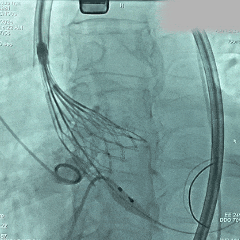

脱钩释放

脱钩后,瓣膜无位移

造影评估,瓣膜深度可,无瓣周漏

左头观察,腰征明显,锚定稳定